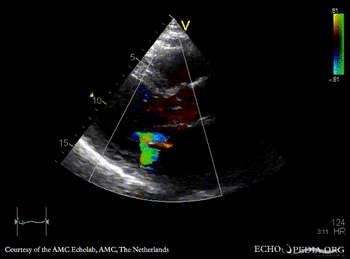

| A2CH | PLAX: Color Doppler, severe mitral regurgitation, excentric jet |